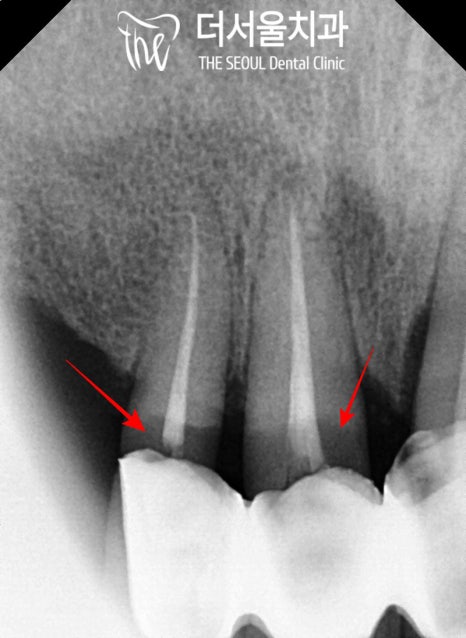

그중에서 주된 불편감을 호소하시는 앞니는

기존 보철 하방으로

이차 충치가 생겨있는데요,

충치로 인해 건전 치질이 약해져있다 보니

작은 힘에도 아슬아슬하게 흔들리며

부러지기 일보 직전이었습니다.

앞서 보여드린 것처럼

파노라마, 치근단, 3차원 CT 촬영을 통해

수술에 적합한 구강인지 판단합니다.